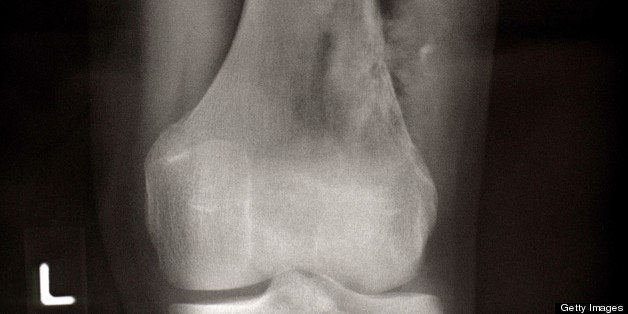

And that's exactly what you did. You didn't let osteosarcoma, a rare bone cancer that strikes teenagers, get in the way of you squeezing happiness out of every day.

And in fact, when you first learned you had osteosarcoma when you were 14, you had true reason to hope. Sixty to 80 percent of patients who are stricken, have a five-year-survival rate of 60 to 80 percent.

Unfortunately, you weren't one of those survivors. Your chemo treatments didn't stop the bone cancer from spreading into your stomach and lungs.